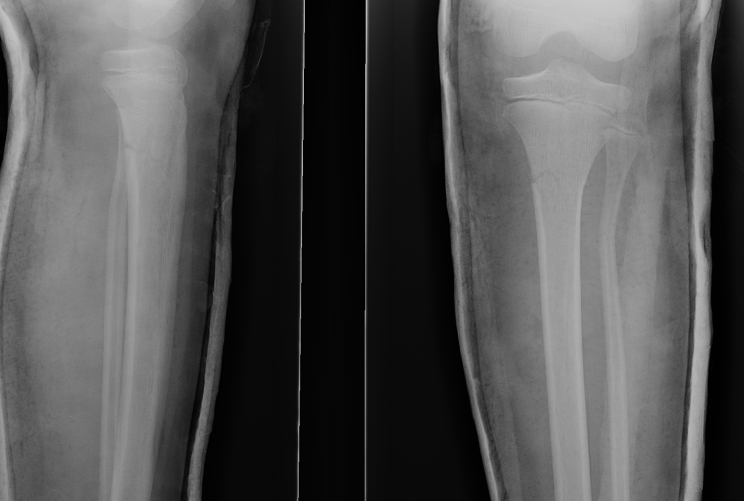

Proximal Metaphyseal Tibial Fracture / Cozen's Fracture

Issue

- may develop long term valgus alignment

- due to medial epiphyseal overgrowth / periosteum medially

Management

Any displacement

- MUA

- extension long leg cast with varus mould

Management of valgus

A. < 10 years with < 15o

- will usually remodel

B. > 10 years with > 15o

- consider operative intervention

- guided growth plates